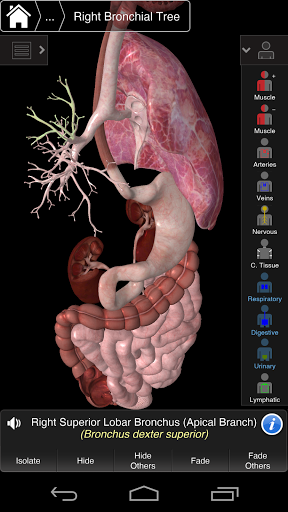

Основна анатомія 3 - це найновіша технологія та новаторський дизайн. Ріжучий 3D-графічний движок, зроблений на замовлення 3D4Medical з усього світу, наділений високоінформативною анатомічною моделлю і забезпечує високу якість графіки, яку не може досягти ніхто інший конкурент.

Програма являє собою унікальний підхід до вивчення загальної анатомії. Графіка не має аналогів і навчається, використовуючи інформативний контент та інноваційні функції, багатий та захоплюючий досвід.

Це додаток включає в себе важливу анатомію для 10 систем:

⁃ респіраторний

НОВІ 3D-ТЕХНОЛОГІЇ

Основна Анатомія 3 чутлива, візуально приголомшлива і легка. Додаток повністю 3D, що означає, що ви можете переглядати будь-яку анатомічну структуру окремо, а також з будь-якого кута.

---- Більше 4000 дуже детальних анатомічних структур